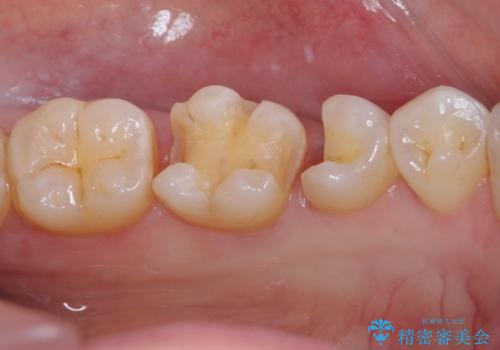

まず麻酔をして銀歯を外し、むし歯を除去し、形を整えて型取りします。

そして次の来院時、セラミックインレーを装着し、噛み合わせなどの調整を行います。

それを左右に分けて行いました。

インレーを装着するときは、唾液や血液による接着力の低下を避けるためにラバーダム防湿を行いました。